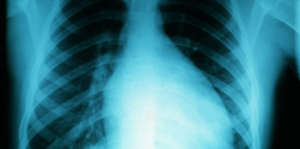

Chest X-ray of a 16-year-old boy with myocarditis.